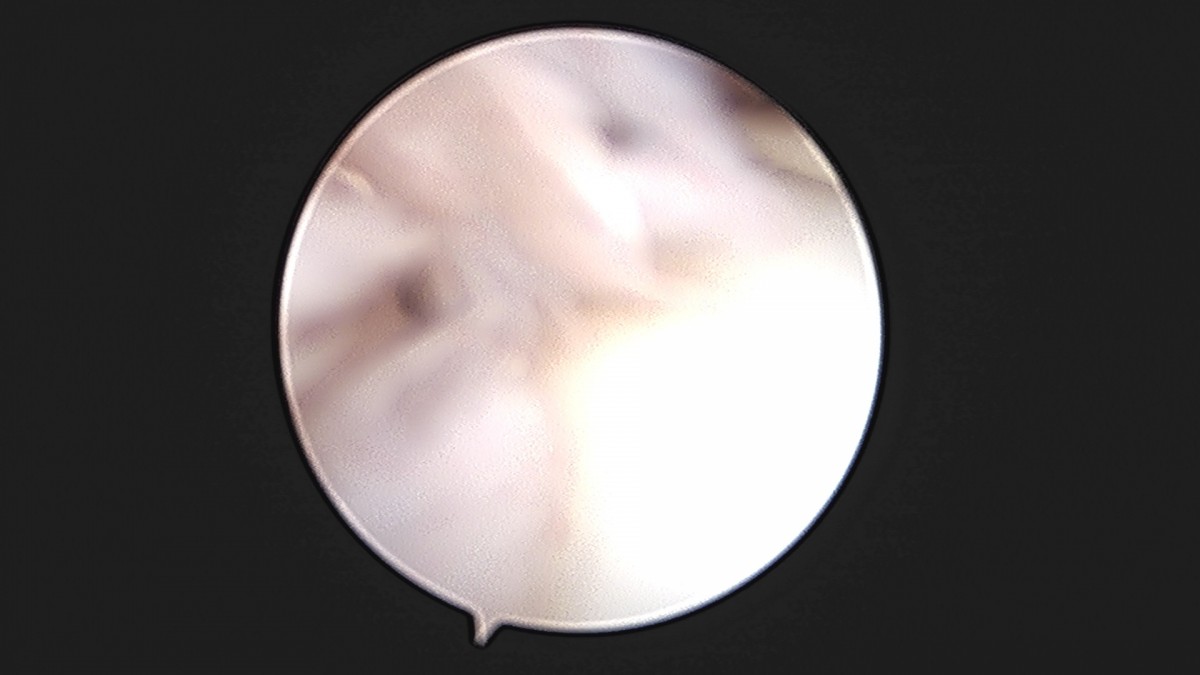

이재상원장님 발목 활액막 절제술 및 인대 봉합술 이승O 환자

작성자 최고관리자 댓글 0건 조회 787회 작성일 25-09-16 15:24